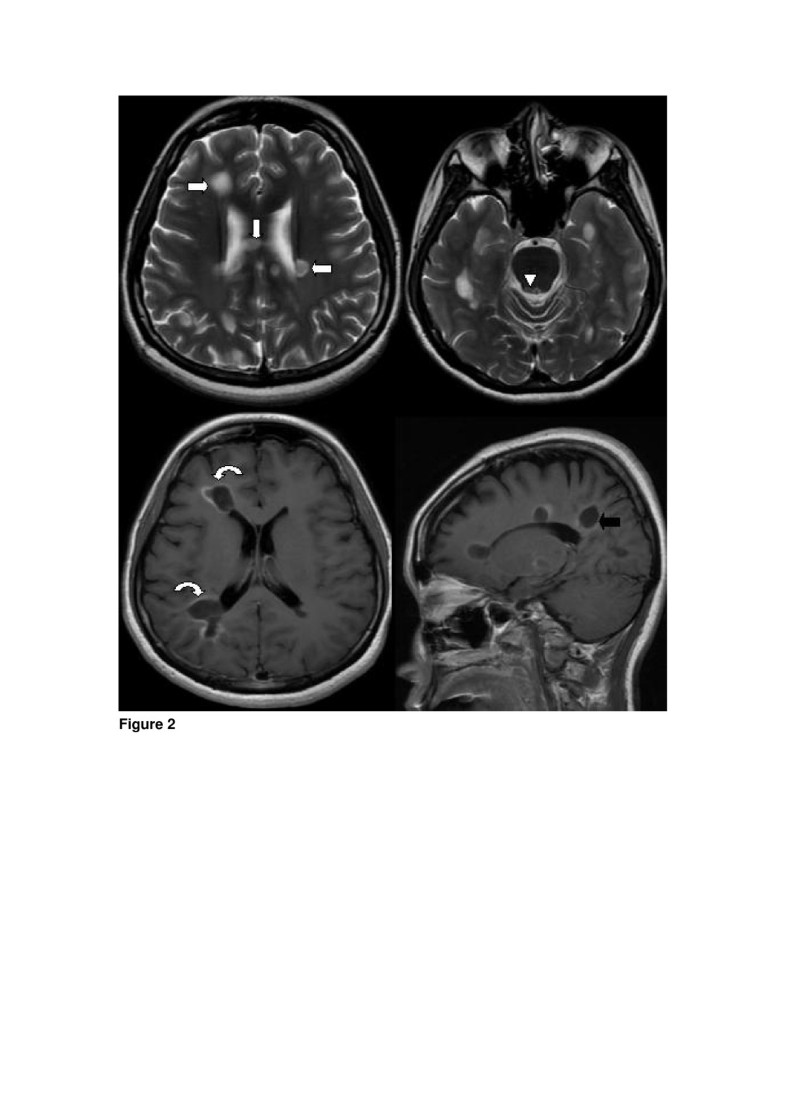

1. Glioblastoma. A 64-year- old woman presented with ...

1. Glioblastoma. A 64-year- old woman presented with ... from www.researchgate.net

Brain lesions can be small or large. Between 2002 and 2006, more than 26 years later, brain mris were performed. N = 96 migraine with the relationship between migraine and subclinical brain ischemic lesions, including silent brain infarctions (sbi) and white matter. The study showed no difference in white matter hyperintensities between men it's not known what causes the relationship between migraine and brain lesions, but one theory is that ischemia occurs during migraine attacks.